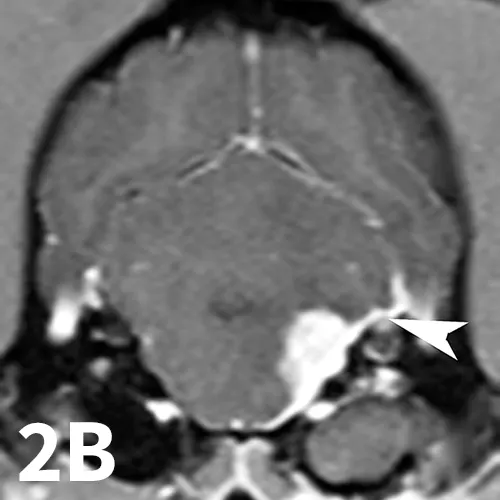

Animals may have erythema and pruritus affecting the external ear or pinna, odor or discharge from the ear, and pain in addition to signs of peripheral vestibular disease. Although diagnosis can be suggested by otoscopy, advanced imaging is superior, as it permits visualization of the osseous bulla and inner ear. The author typically prefers MRI to image dogs suspected of otitis interna because it is superior to computed tomography (CT) for detecting intracranial extension of lesions and detecting other causes masquerading as otitis interna. On MRI, bullae may appear thickened and are usually filled with T2-hyperintense/T1–iso-hypointense (dark) material; abnormal tissue within the bulla usually contrast-enhances T1WI (Figure 2). On T2WI, there may be a loss of signal within the inner ear. Myringotomy and deep ear flush are recommended to identify the underlying infectious agent and assist in removing debris or pus that will prohibit clearance of infection. Antimicrobial therapy is typically continued for 6 to 8 weeks, as bone infection is likely.

Transverse T2WI (A) and T1WI (B) from a 6-year-old cocker spaniel with a 6-month history of left peripheral vestibular disease that acutely worsened, with signs consistent with central localization. The left middle ear cavity is filled with T2-hyperintense material (arrowhead). The left inner ear is hypointense (arrow) compared with the right side. In addition, the left medulla and cerebellum contains patchy T2-hyperintense lesions. T1 postcontrast images show enhancement of the meninges (arrowhead) and a mass-like, enhancing lesion adjacent to the internal acoustic meatus. These findings are consistent with chronic otitis interna and media with secondary extension into the meninges and central nervous system.